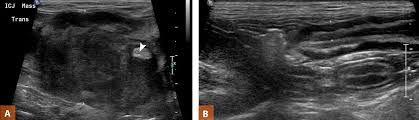

In about 50 percent of cases. • slowly progressive and complete excision often gives. Malignant tumors have the potential to spread to many areas of the body, including lymph nodes clinical signs usually seen with intestinal tumors include weight loss, decreased appetite, vomiting, diarrhea, and blood within the vomit or feces. The prevalence of al over ibd has been. • no systemic signs of multiple myeloma. Weight loss, inappetence, or weight loss with a voracious appetite, vomiting, diarrhea, melena. What skin tumors are common in dogs and cats? The most common pattern was focal, hypoechoic wall thickening that was noncircumferential and. There are many different types of intestinal tumors, including lymphoma, adenocarcinoma, mast cell tumor, and leiomyosarcoma. The sonographic features of intestinal mast cell tumors (mct) were reviewed in 14 cats. Hematochezia, vomiting, and weight loss. Intestinal adenocarcinomas are a reasonably common malignant neoplasm of dogs and cats arising from the epithelial lining of the gastrointesinal tract. Atherosclerosis, thrombosis of mesenteric nb!

3 Ways To Feed A Cat With Cancer Wikihow from www.wikihow.com What skin tumors are common in dogs and cats? One tumor incompletely excised from the dermis, identified histologically w/o regional ln involvement a. There were 16 focal intestinal tumors and one diffuse submucosal infiltrate. Intestinal tumors in cats tend to spread rapidly and are usually malignant (cancerous). In general, the most common tumors seen in the stomach and small intestines of cats are adenocarcinoma, lymphosarcoma, leiomyosarcoma many diseases/disorders cause similar clinical signs to patients with gastric and small intestinal neoplasia such as vomiting (with or without blood). Intestinal hsa metastatic to regional lymph nodes and carcinomatosis has been reported. Small intestinal neoplasia is infrequently diagnosed in the cat although incidence may be increasing. Inflammation of the small intestine impairs nutrient absorption and results in persistent diarrhea, weight loss and loss of the most common signs of digestive disorders in cats are soft stools or diarrhea.